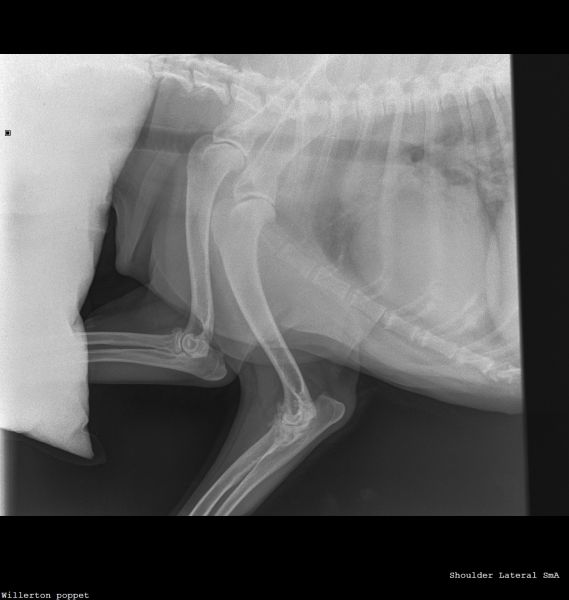

Hi vets, Wondered if anyone could give a second opinion on these X-rays? 12 year old dog. Left forelimb lameness improved with antibiotics then got worse again. Gradually worsening over the past 3 months. Pain on palpation around the left wrist joint and has been treated for an infected claw on the left paw 8 weeks ago (the starting incident for vet treatment). Muscle loss around left shoulder and now winging from the elbow. My first practitioner vets have sent it off for an orthopaedic consult but in the meantime it would be nice to settle my brain that nothing terrible is happening with my dog 🤞🏻 Thank you 🙏🏻Willerton_poppet_CARPUS-Carpus Dorso-palmaWillerton_poppet_SHOULDER-Shoulder Lateral(1)Willerton_poppet_SHOULDER-Shoulder Lateral

Hello and thank you for this interesting question.  With my harsh scientific hat on rather than my people-hat, I can point out that nobody can tell you even from a very comprehensive series of x-rays that nothing terrible is happening with your dog; however, investigation of any areas of concern is always a good way forward. We do not read radiographs as part of this series; I have no additional qualifications in reading radiographs so this is best done by the vet who has the full context available to them and if they are unsure, then an expert.  Sometimes if experts are unsure, they will offer further tests or a biopsy.  My job is to help you to get the best out of your vet and I, perhaps like your vet, am a little concerned about the way some of these joints present on the radiograph.  It therefore seems a good idea to maximise the effectiveness of the radiographs already taken, to ask for the comment of an expert.  This seems a reasonable and appropriate next step. Lameness is usually a reflection of pain; the fact that an animal is lame tends to imply that it hurts to put the leg down properly.  The changes to the nail may have been part of a cause of this (for example, fungal infection affecting bone causing pain,  not the only possibility) or part of a consequence of this (ie lameness / altered weight-bearing causing damage to the nail).     It  may be worth asking whether your pet can have pain relief in the meantime, in order to make them more comfortable.  Wishing you the best of luck with this case going forward; please would you let us know how your chihuahua gets on?